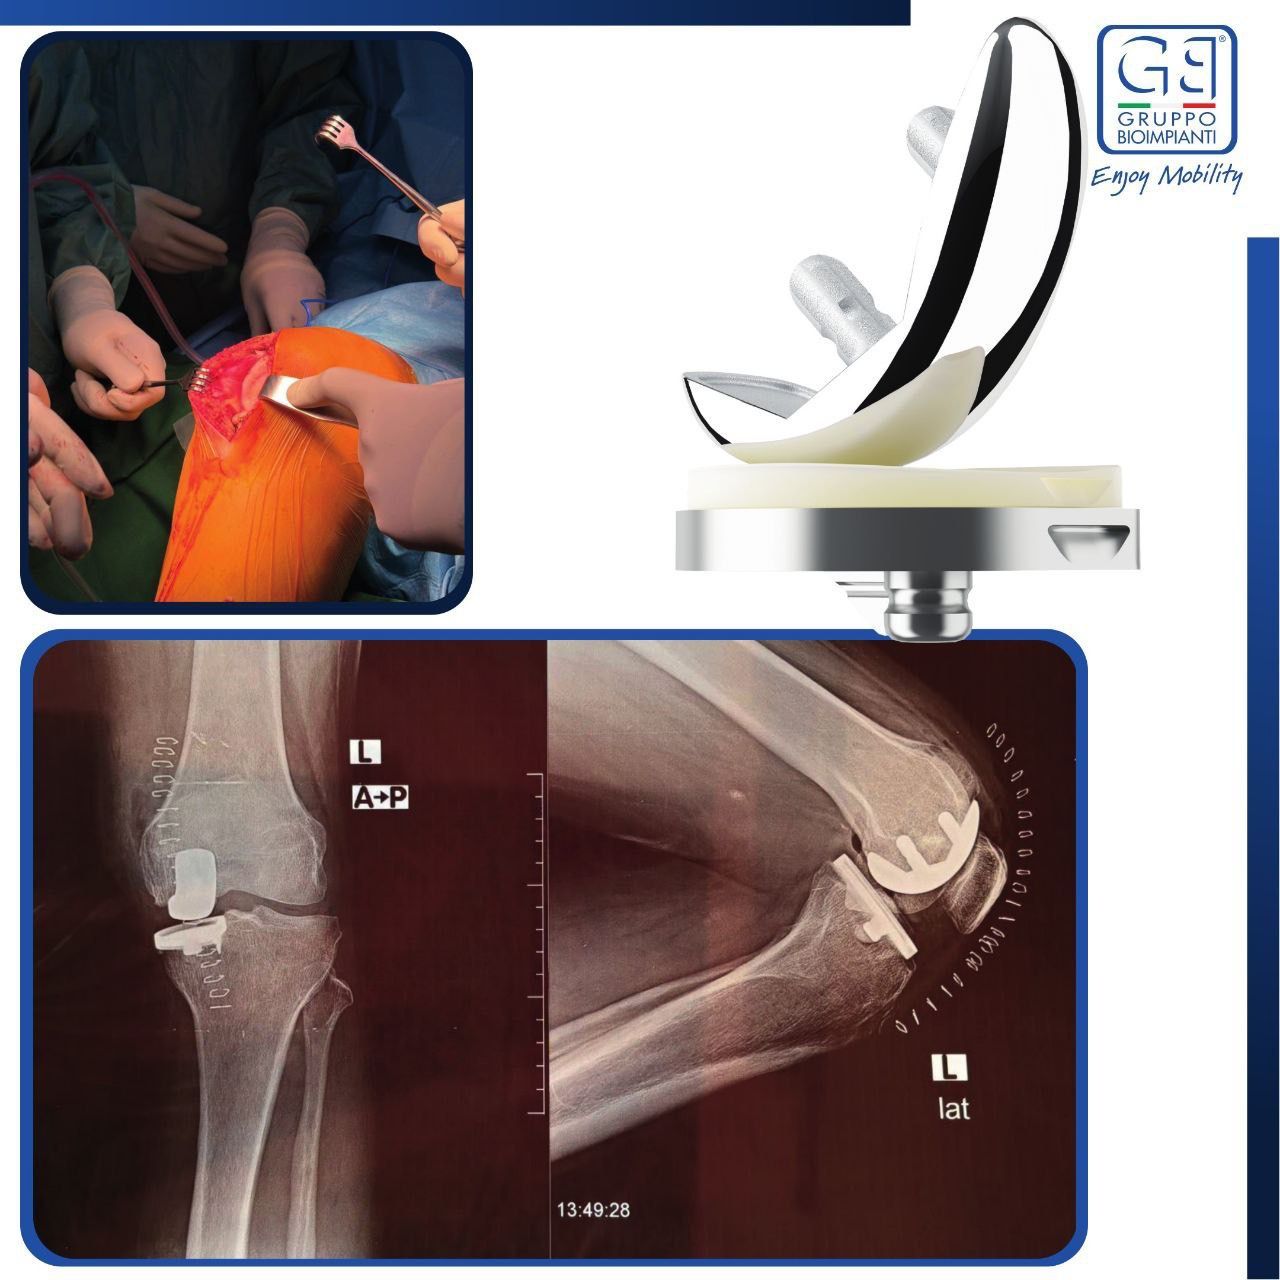

Keeping pace with the latest advancements in the health sector, and for the first time in Libya, three Partial Knee Replacement surgeries were successfully performed during the Fifth Knee Surgery Training Course, held in the city of Sabratha under the supervision of the Medical Specialties Board and the Libyan Society of Arthroscopy and Knee Surgery, at Al-Rasheed Hospital in Salah Al-Din.

This surgical procedure aims to replace only the damaged portion of the knee joint while preserving the healthy parts, and is used to treat unicompartmental knee osteoarthritis confined to a single compartment.